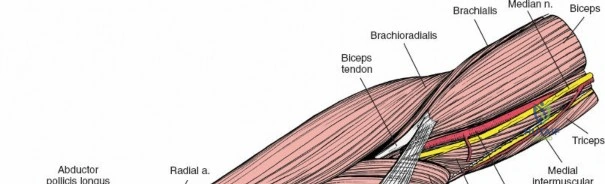

Accurate identification of surface landmarks is the first step in a successful Henry approach. Palpate the biceps tendon, a stout, taut structure crossing the anterior elbow joint just medial to the brachioradialis muscle. Next, palpate the brachioradialis itself, the fleshy muscle forming the lateral border of the cubital fossa. Finally, identify the styloid process of the radius distally. Note that when the forearm is fully supinated (the anatomic position), the radial styloid is truly lateral.

Make a straight or gently curved incision beginning at the anterior flexor crease of the elbow, just lateral to the biceps tendon. Extend this incision distally toward the styloid process of the radius. The exact length and placement of the incision are dictated by the specific pathology; the approach is highly modular, and often only the proximal, middle, or distal third of the incision is required.

Superficial Surgical Dissection and Internervous Plane

Incise the deep fascia of the forearm in line with the skin incision. The initial goal is to identify the medial border of the brachioradialis as it courses down the forearm. It is a common pitfall to search for this border too far laterally. At the level of the elbow, the brachioradialis is expansive and extends almost halfway across the anterior forearm. It is surprisingly easy to mistake the plane between the brachioradialis and the extensor carpi radialis longus for the correct intermuscular plane.

To confirm the correct plane, look for the superficial branch of the radial nerve. This sensory nerve runs on the undersurface of the brachioradialis muscle. Once the true medial edge of the brachioradialis is found, develop the plane between it and the pronator teres (proximally) or the flexor carpi radialis (distally). Retract the brachioradialis laterally, taking care to keep the superficial radial nerve attached to its undersurface to protect it from traction injury.